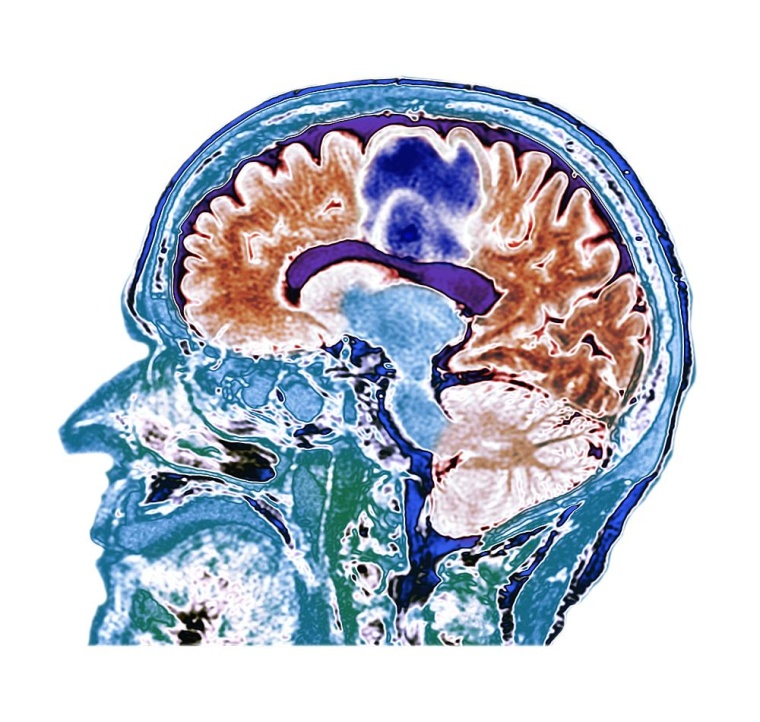

Medikamente millimetergenau ins Gehirn bringen

Fokussierte Ultraschallwellen helfen ETH-Forschenden, Medikamente im Gehirn punktgenau zu platzieren, also nur dort, wo ihre Wirkung erwünscht ist. Die Methode soll künftig psychiatrische, neurologische und onkologische Behandlungen mit weniger Nebenwirkungen ermöglichen.

Forschende der ETH Zürich haben eine Methode entwickelt, mit der Medikamente im Hirn punktgenau freigesetzt werden können. Damit könnte es in Zukunft möglich werden, Psychopharmaka, Chemotherapeutika und andere Medikamente nur in jene Hirnregionen zu bringen, wo das aus medizinischen Gründen gewünscht ist.